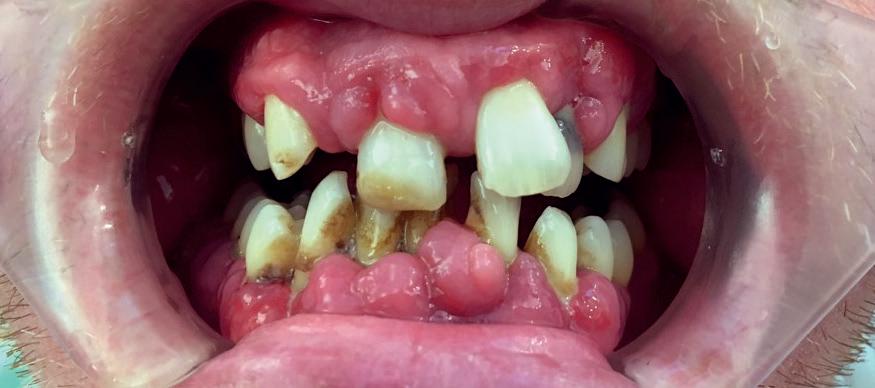

Where the Australian public healthcare system REALLY seems to fall down though is, yes, you guessed it: dentistry.

Adult dental patients are pretty much abandoned as far as Medicare is concerned, with dental care being largely excluded from standard Public Healthcare System benefits. This means that most adult patients typically have to pay out-ofpocket or use private health insurance that includes dental cover.

For low-income earners and some eligible groups, they MAY be able to access subsidised or free dental care through public dental clinics although access can vary from state to state. Waiting times can be long.

For children, care is governed by the Children’s Dental Benefits Schedule (CDBS). Medicare covers eligible children between the ages of two to 17 for up to $1,095 over two years for basic dental services. This is roughly £550. Though including exams, X-rays, cleaning, fillings, and extractions, families must receive certain meanstested ‘Centrelink’ Family Tax Benefit payments to qualify, and not every family with children automatically receives this benefit.

The public health Medicare system MAY cover dental surgery performed in a public hospital – especially if it’s deemed to be medically necessary - examples being severe infection, injury, or oral surgery related to other conditions.

The Aussies I spoke to about their dental health system seemed to be at ease with the situation, adopting a laissez-fair, ‘no worries’ attitude to their dental access. It was obviously only my wife and I that were mildly alarmed at the apparent inadequacies in terms of access to public health dentistry for your ‘standard’ adult and child, though that’s probably because I had an NHS contract from qualification to retirement, while my wife had to listen to me whingeing on about it for nigh on 30 years.

To me (from the outside and now over 10,000 miles away), it looks like teeth have been as good as abandoned by the Australian public health service and my fear is that we are only a brief stopover in Dubai before reaching that point ourselves. Since the Aussies lived under mostly privately funded healthcare before the 1970s,

with Medicare only being introduced in 1984, they seem to be used to the idea that teeth can pretty much fend for themselves. But should they?

Aneurin Bevan had a clear and overriding philosophy behind his setting up of the National Health Service: healthcare should be a right, not a privilege. And surely, overall healthcare MUST include dentistry?

Organisations like Toothless In England and the British Dental Association, and thousands of dental professionals, and millions of UK citizens accept that dentistry is healthcare, but the people in Government still haven’t grasped the concept of what constitutes a crisis. And strewth, is this a crisis, or what? Well, the UK’s Public Accounts Committee (PAC) certainly thinks so having said that the national dental plan set out by the former Tory Government had “comprehensively failed.”

It certainly feels like dentistry and patients have been abandoned when a Freedom of Information request by the Liberal Democratic Party revealed that there were 16,100 A&E attendances related to tooth decay in 2024, and nearly 3,000 of those patients were children.